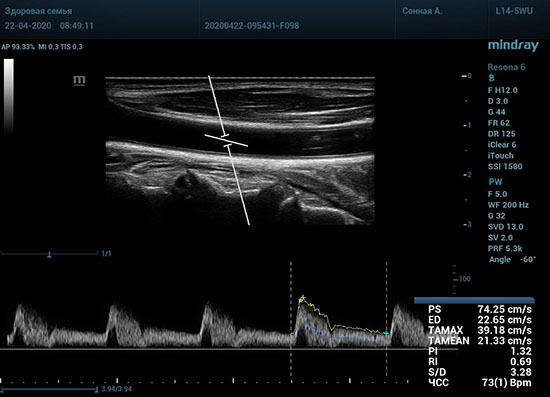

Какие показатели выдает автоматический расчет? Доктор может настроить расчет под себя, под свои собственные желания. Стандартно выставлены показатели пиковой (PS) и конечной диастолической скорости (ED), TAMAX, TAMEAN, Pi, Ri, S/D соотношение и ЧСС. Можно дополнить из списка показателей: MD, PPG, Объемный поток, DT, AT, MPG, MMPG, VTI, D/S соотношение. Прибор подстраивается под Вас, а не вы под прибор.